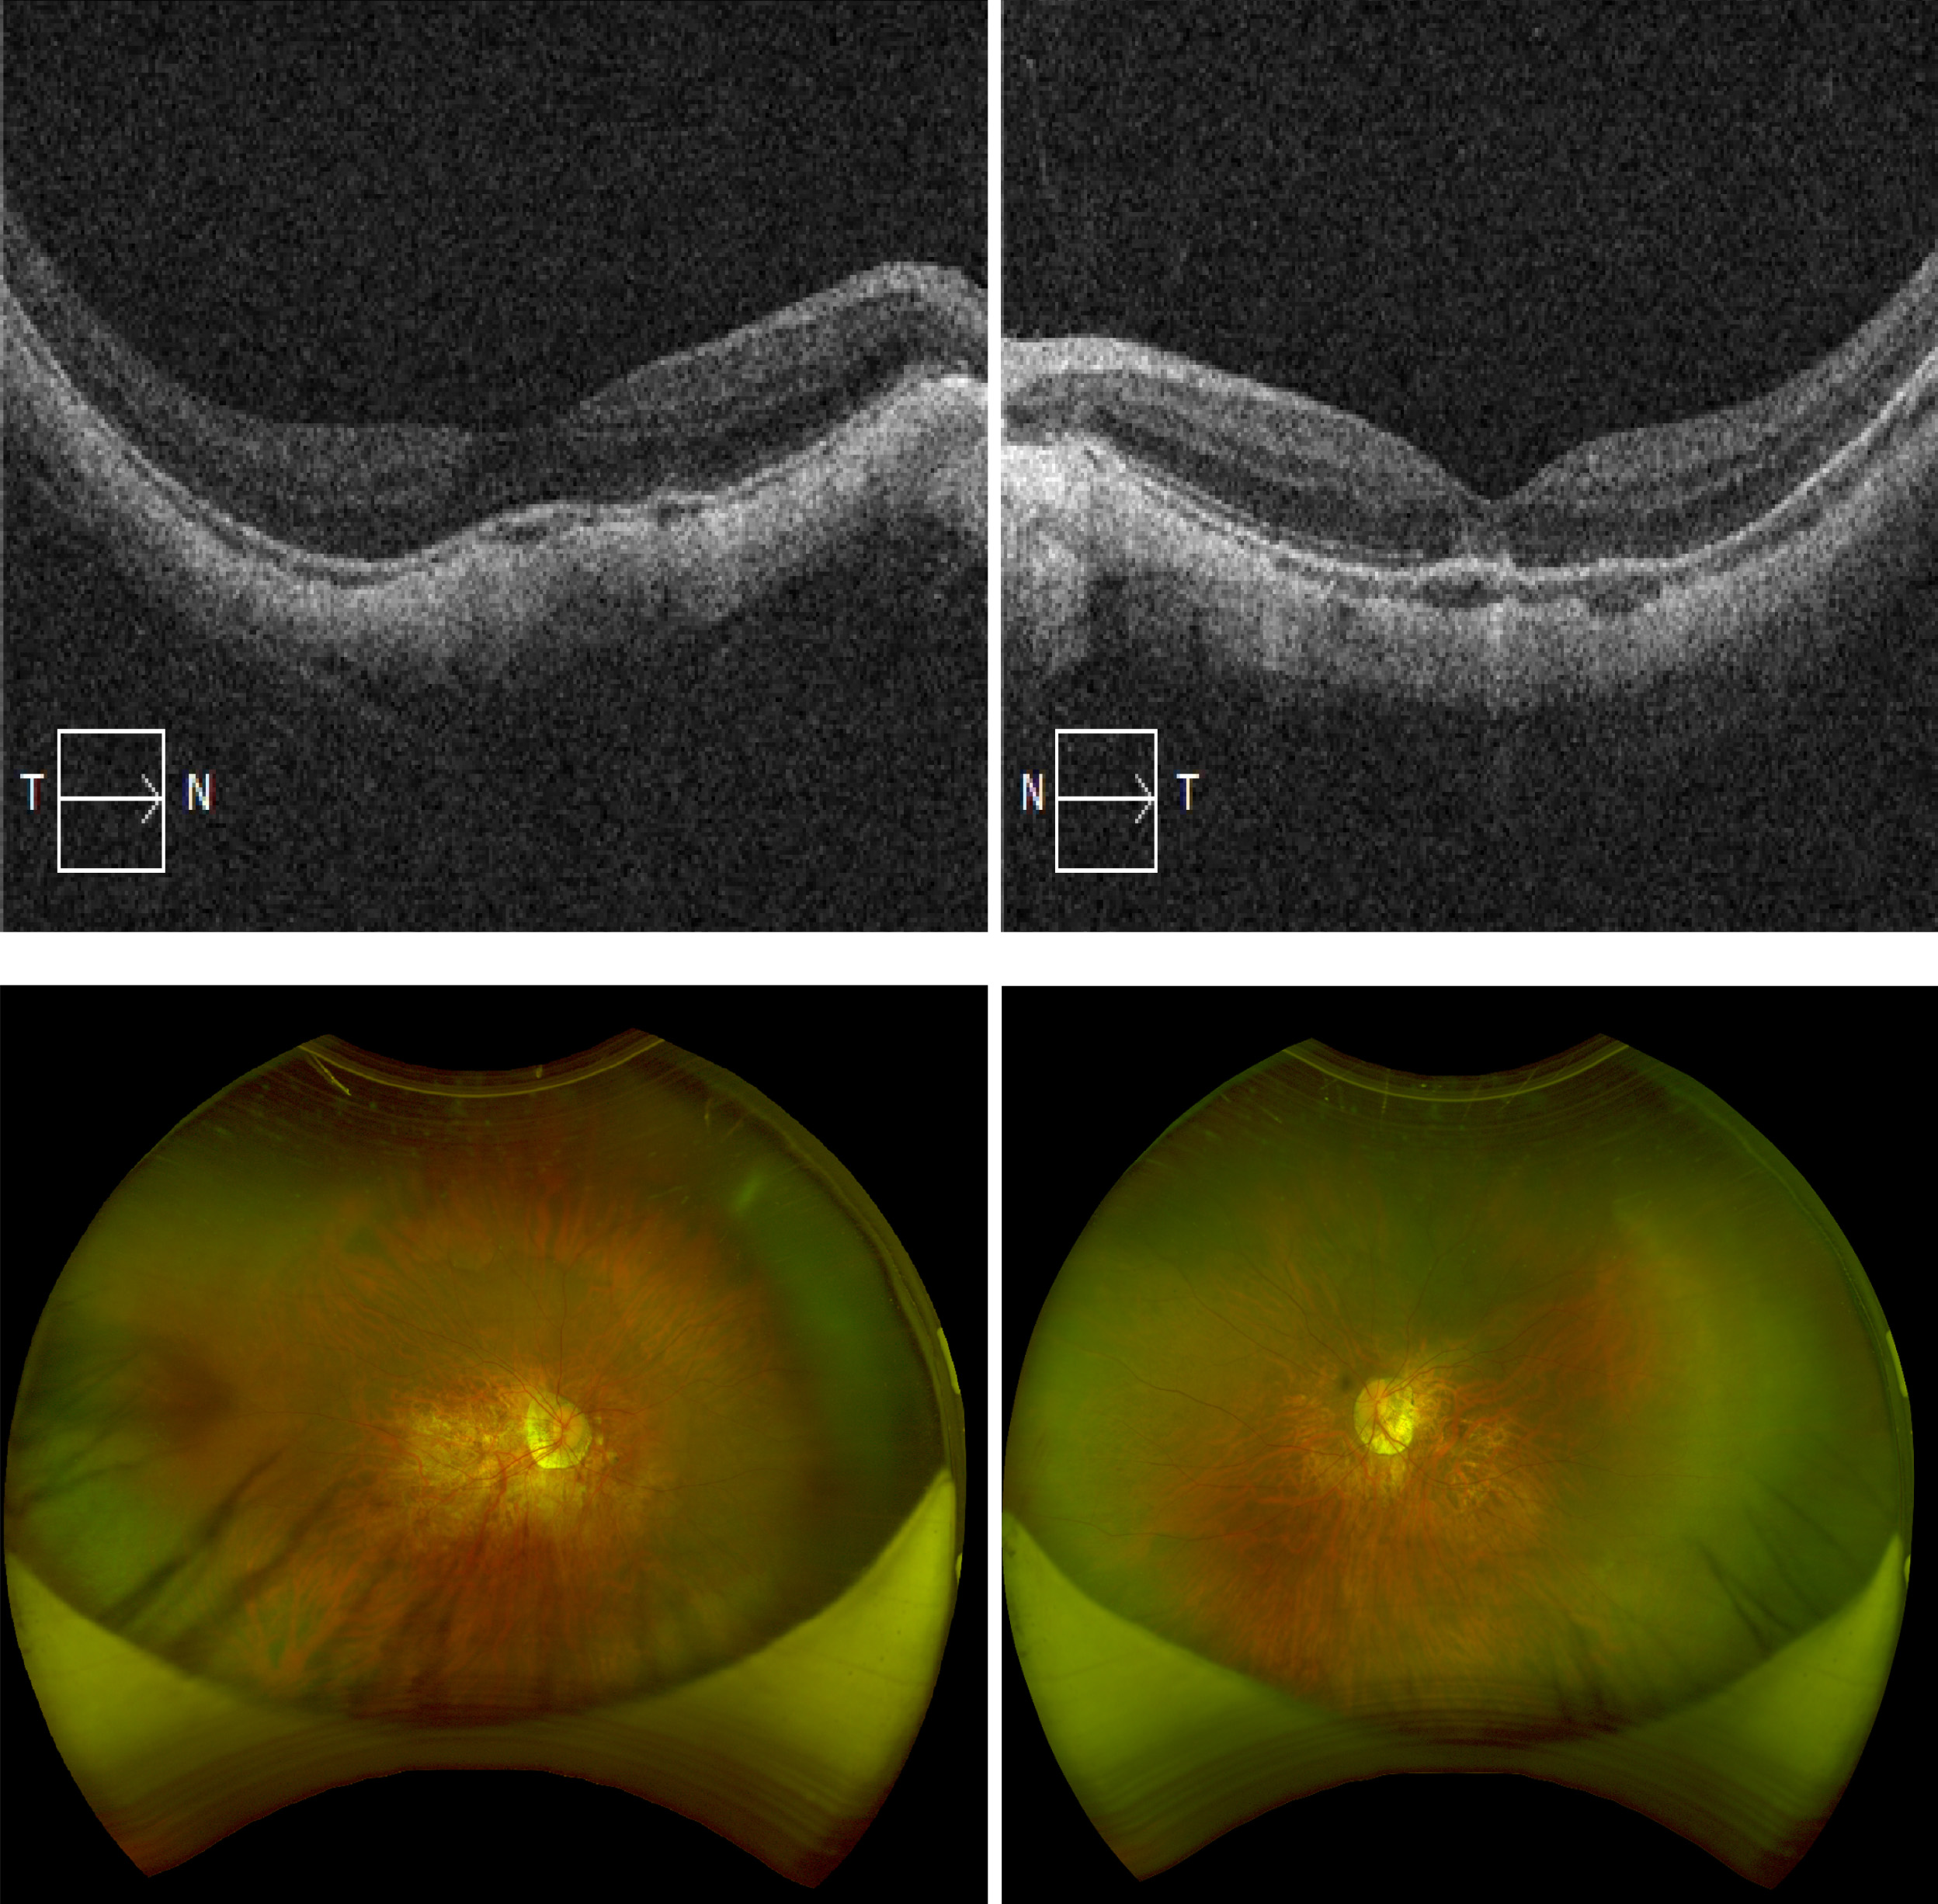

Methods: We reviewed 125 eyes from 64 patients who implanted ICL-V4c at the Refractive Surgery Center of West China Hospital in Chengdu, China, between May 2015 and January 2017. These eyes were divided into two groups based on their preoperative spherical equivalent (SE) degree: high myopia (≥ -10D) and super-high myopia groups (< -10D). We followed up with the patients over 5 years and evaluated several parameters, including uncorrected visual acuity (UDVA), corrected visual acuity (CDVA), axial length (AL), refractive error, endothelial cell density (ECD), intraocular pressure (IOP), white-to-white distance (WTW), and vault.

Results: The efficacy indices of ICL-V4c implantation in high and super-high myopia groups were 0.91 ± 0.23 and 0.80 ± 0.25, respectively at 5 years after operation. Compared to high myopia group, the efficacy index of super-high myopia was obviously decreased (p = 0.020) and the △AL of super-high myopia was significantly increased (p = 0.001). The mean safety indices were 1.10 ± 0.15 and 1.10 ± 0.21 respectively in high and super-high myopia groups (p = 0.850). At the 5-year mark, 11.67% vs 20.00% (High vs Super-high) of eyes were within ±0.50 D (Spherical Equivalent), and 75.00% vs 70.77% (High vs Super-high) of eyes were within ±2.00 D. No significant difference of ECD was found in the high (2823.45 ± 274.75 cells/mm2) and super-high myopia (2856.71 ± 323.53cells/mm2) at the visit of 5 years. Compared to baseline, we observed a significant increase in IOP at the 1-week follow-up, which decreased significantly at the one-month visit. Furthermore, there was a significant difference of vault between the high and super-high groups at 1-month (p = 0.042) and 5-year (p = 0.002) after surgery.

Conclusions: ICL-V4c implantation is effective, safe, and stable for correcting high and super-high myopia. However, ophthalmologists need to be aware of the potential for greater myopia regression in super-high myopic patients, as well as the increase in axial length and associated fundus complications.